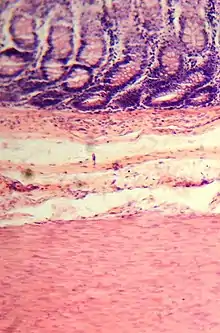

The wall of the large intestine is lined with simple columnar epithelium with invaginations. The invaginations are called the intestinal glands or colonic crypts.

Micrograph of normal large instestinal crypts.

Anatomy of normal large intestinal crypts

The colon crypts are shaped like microscopic thick walled test tubes with a central hole down the length of the tube (the crypt lumen). Four tissue sections are shown here, two cut across the long axes of the crypts and two cut parallel to the long axes. In these images the cells have been stained by immunohistochemistry to show a brown-orange color if the cells produce a mitochondrial protein called cytochrome c oxidase subunit I (CCOI). The nuclei of the cells (located at the outer edges of the cells lining the walls of the crypts) are stained blue-gray with haematoxylin. As seen in panels C and D, crypts are about 75 to about 110 cells long. Baker et al.[31] found that the average crypt circumference is 23 cells. Thus, by the images shown here, there are an average of about 1,725 to 2,530 cells per colonic crypt. Nooteboom et al.[32] measuring the number of cells in a small number of crypts reported a range of 1,500 to 4,900 cells per colonic crypt. Cells are produced at the crypt base and migrate upward along the crypt axis before being shed into the colonic lumen days later.[31] There are 5 to 6 stem cells at the bases of the crypts.[31]

As estimated from the image in panel A, there are about 100 colonic crypts per square millimeter of the colonic epithelium.[33] Since the average length of the human colon is 160.5 cm[11] and the average inner circumference of the colon is 6.2 cm,[33] the inner surface epithelial area of the human colon has an average area of about 995 cm2, which includes 9,950,000 (close to 10 million) crypts.

In the four tissue sections shown here, many of the intestinal glands have cells with a mitochondrial DNA mutation in the CCOI gene and appear mostly white, with their main color being the blue-gray staining of the nuclei. As seen in panel B, a portion of the stem cells of three crypts appear to have a mutation in CCOI, so that 40% to 50% of the cells arising from those stem cells form a white segment in the cross cut area.

Overall, the percent of crypts deficient for CCOI is less than 1% before age 40, but then increases linearly with age.[30] Colonic crypts deficient for CCOI in women reaches, on average, 18% in women and 23% in men by 80–84 years of age.[30]

Crypts of the colon can reproduce by fission, as seen in panel C, where a crypt is fissioning to form two crypts, and in panel B where at least one crypt appears to be fissioning. Most crypts deficient in CCOI are in clusters of crypts (clones of crypts) with two or more CCOI-deficient crypts adjacent to each other (see panel D).[30]